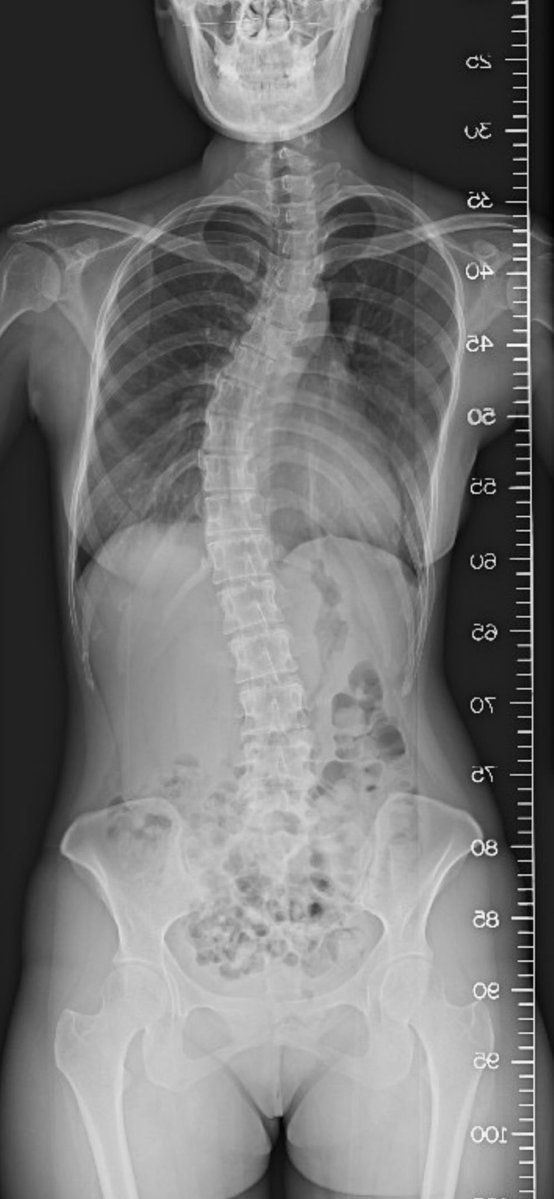

- 背骨歪んでんな

- 背中どうしたこれ

- 全体的に歪んでないか

- ぐにゃぐにゃ

- 背骨大丈夫なんか

- 骨がぐちゃぐちゃ?

- ウサイン・ボルトの背骨みたい

- 脊柱側弯症やね

- 側湾やばすぎやろ

- 背骨が心配が勝つ

- 背骨すごいな